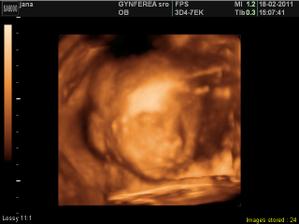

Najkrajší dar na svete - dieťa.